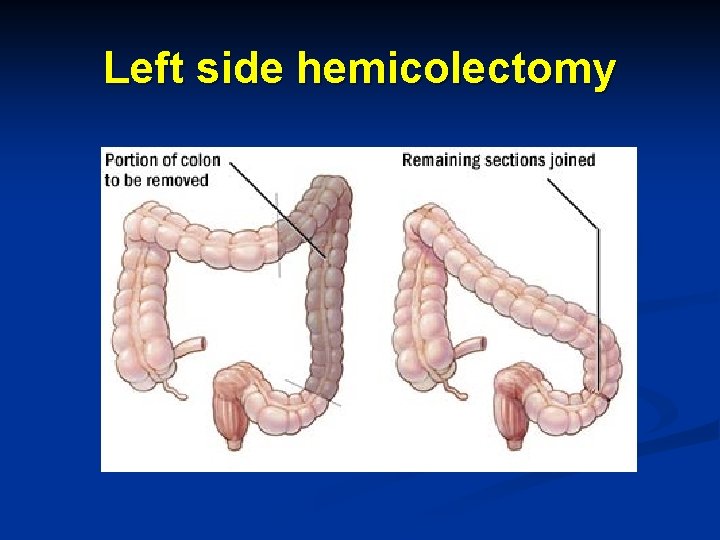

Left side hemicolectomy